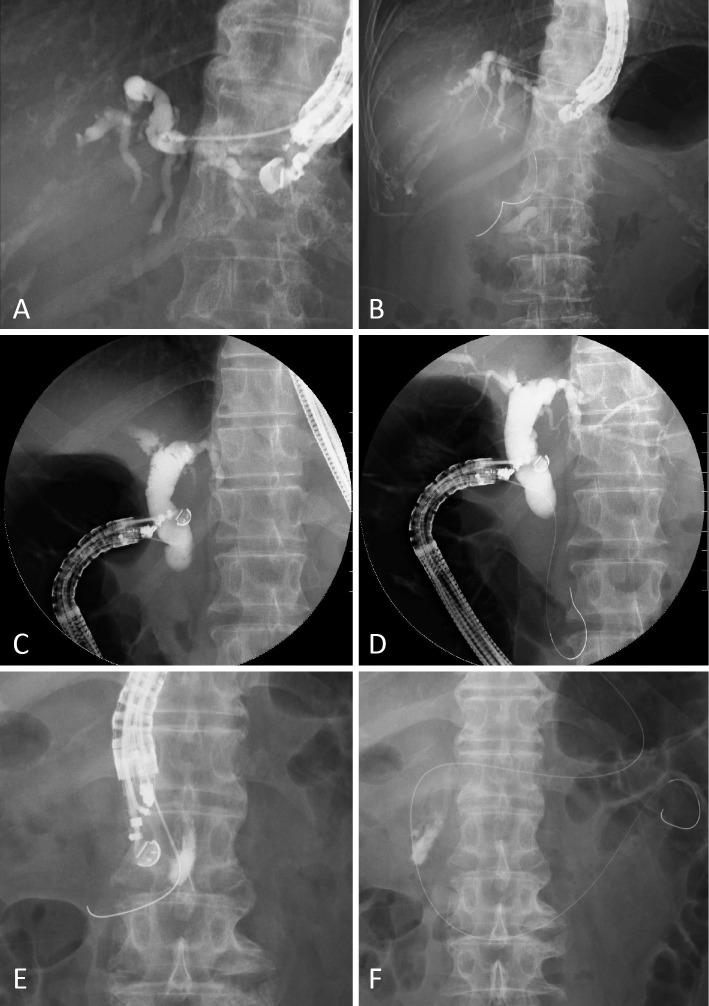

目的 内镜超声引导会师技术(EUS-RV)是一种用于选择性胆管插管失败的挽救方法。已报道了三种穿刺途径,对肝内胆管和肝外胆管进行了多次比较。我们采用经食管(TE)和经空肠(TJ)途径。在本研究中,重点关注穿刺途径,评估了EUS-RV用于胆管通路的实用性。

方法与患者 对39例患者的42条穿刺途径进行了详细评估。EUS-RV于2010年1月至2014年12月期间进行。患者为前瞻性纳入,其临床资料进行回顾性收集。

结果 患者的中位年龄为71岁(范围29 - 84岁)。内镜逆行胰胆管造影(ERCP)的适应证为恶性胆管梗阻24例,良性胆道疾病15例。技术成功率为78.6%(33/42),各穿刺途径间相似(p = 0.377)。总体并发症发生率为16.7%(7/42),各穿刺途径间相似(p = 0.489)。然而,2例经TE途径的EUS-RV患者发生了纵隔气肿。未发生与EUS-RV相关的死亡。

结论 ERCP失败后,EUS-RV被证明是可靠的。根据患者情况选择合适的途径至关重要。